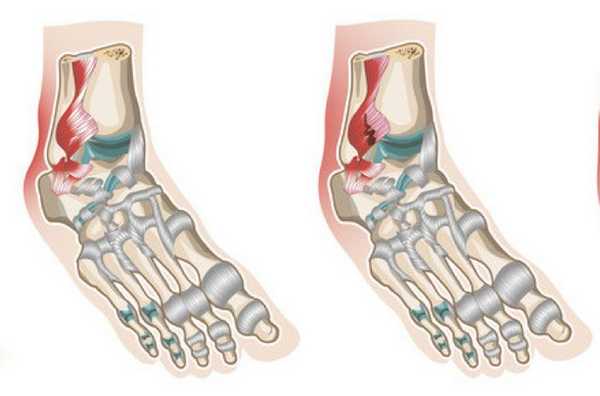

Разрыв связок происходит, когда подворачиваются ноги внутрь. При этом нагрузка на наружные связки сустава значительно увеличивается. В определенных случаях возможен перелом костей, которые формируют сустав.

Иногда растяжение связок голеностопного сустава сопоставляют с повреждениями, проявляющимися в результате подворачивании стопы. Однако в этом случае ошибочно говорить о растяжении, поскольку имеют место кровоподтеки и отечность. В момент получения травмы возникают разрывы в области связочного аппарата. В свою очередь, при растяжении нарушается целостность некоторых волокон, но функциональные характеристики остаются без изменений.

При более серьезных травмах может наблюдаться полный разрыв связок голеностопного сустава. При этом проявляются признаки, идентичные перелому костей. Больной утрачивает способность передвигаться, поскольку ощущает сильный болевой синдром и невозможность наступать на конечность. Подобные симптомы обусловлены изменением анатомического соотношения составных частей сустава. К числу характерных черт недуга также относится быстрое распространение гематомы и отечности на всю площадь лодыжки.